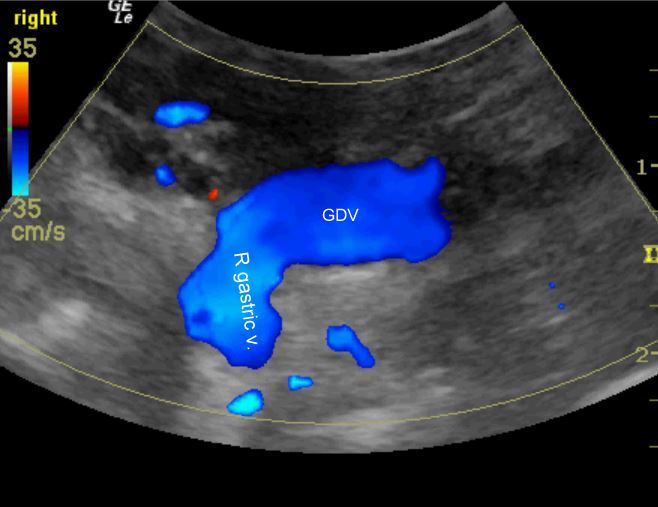

Congenital extrahepatic portosystemic shunt via the right gastric vein Extrahepatic Disease In Dogs Cchs usually is associated with suppurative inflammation, implicating a disease causing bile flow stasis with potential for bacterial. Portosystemic shunts are the most common congenital liver anomaly (see portosystemic vascular malformations in small animals). Obstruction of the common bile duct is associated with a number of diverse primary conditions. Extrahepatic biliary disease in dogs is commonly encountered in clinical practice. Extrahepatic Disease In Dogs.

Congenital extrahepatic portosystemic shunt via the right gastric vein Extrahepatic Disease In Dogs Extrahepatic biliary tract surgery has been associated with high morbidity and mortality rates in humans and dogs, despite advances in surgical technique and supportive care. Diseases with complete extrahepatic biliary obstruction (ehbo) in dogs, the most common reasons for obstructive biliary tract diseases are. If ehbo is present in a sick dog. Diseases in this segment of the biliary tract. Extrahepatic Disease In Dogs.

Congenital extrahepatic portosystemic shunt via the right gastric vein Extrahepatic Disease In Dogs Development of ehbdo can lead to a critical. Extrahepatic biliary disease in dogs is commonly encountered in clinical practice worldwide. If ehbo is present in a sick dog. The most common causes of ehbo include: Diseases in this segment of the biliary tract are diverse and. Portosystemic shunts are the most common congenital liver anomaly (see portosystemic vascular malformations in. Extrahepatic Disease In Dogs.